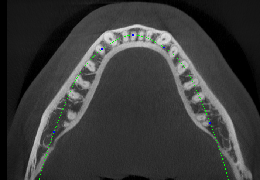

ANYTHINK 经导管主动脉瓣膜置换术分析系统